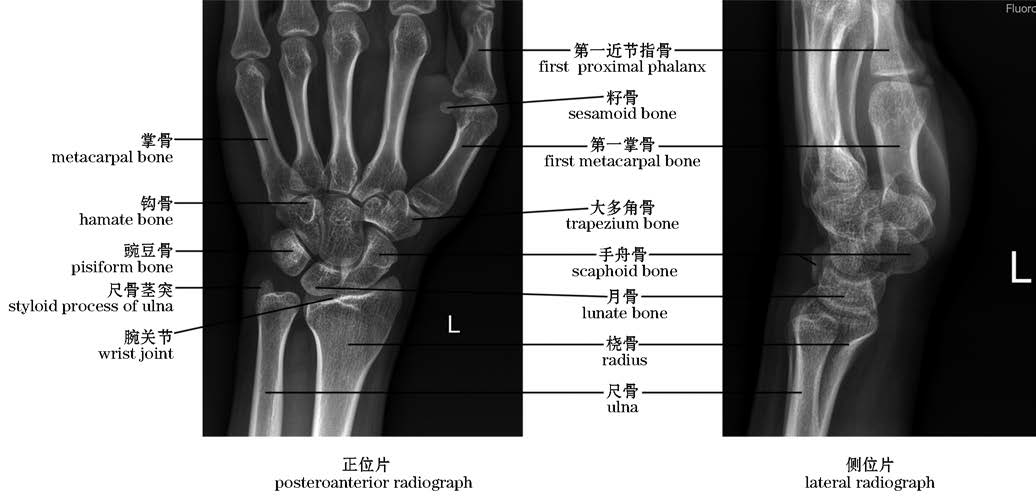

图2-32 腕关节X线片(左)

The wrist joint,X-rays(left)